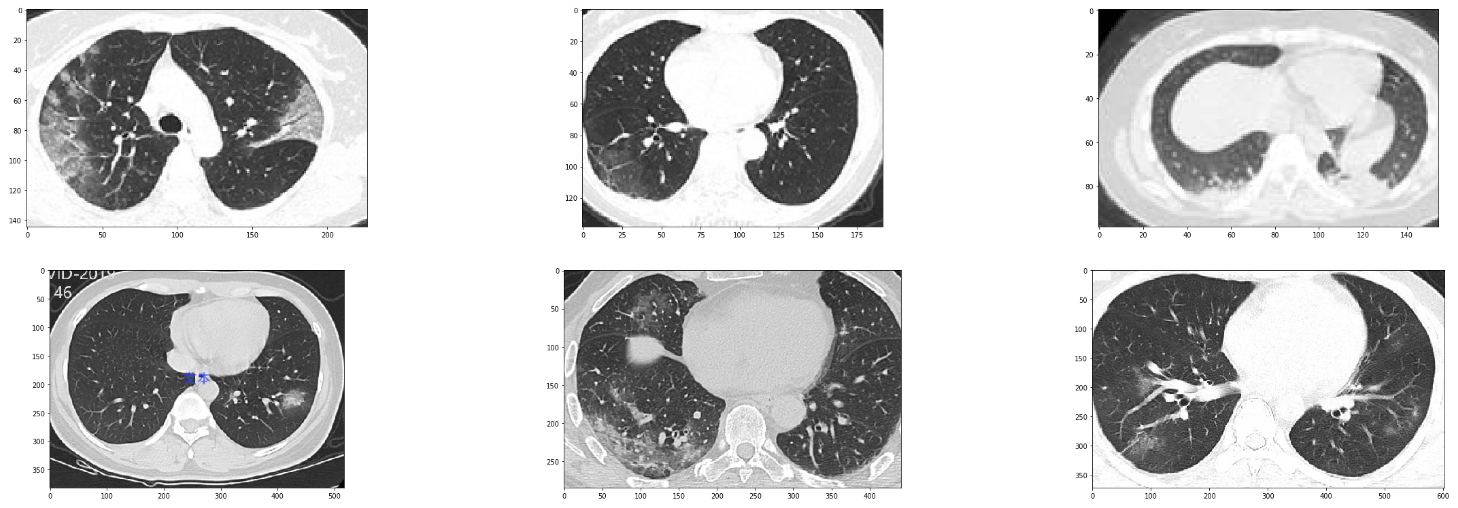

With that in mind, let's visualize the some examples from our dataset.

Sample images from the dataset

We first begin with the COVID-19 positive cases.

We can similarly see random samples of the non-corona cases by changing the value of covid_files_path variable to Images-processed/CT_NonCOVID.